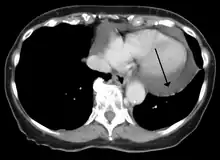

-

A CT scan image showing a pericardial effusion -